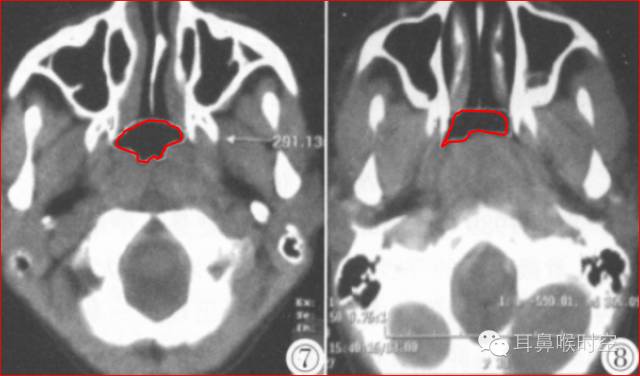

图1 鼻咽气腔N值 图2 腺样体A值

③同层动态CINE:

利用GE公司HispeedAW工作站,选择任意3个层面测量(图3,4)

求两两之间的面积最大差值(△S=118.04- 91.15) 。

图3 鼻咽气腔有效面积 Sn 图4 CINE测量有效面积 Sn1

标准CT 轴位像:

鼻咽气腔形态因层面不同而不同,其中,呈梯形(图3),长方形(图4)。

咽隐窝及咽鼓管咽口清晰或隐约可见,双侧对称,鼻后孔大部分畅通,咽旁间隙清晰,邻近骨质无破坏。

鼻咽气腔形态

梯形 长方形

鼻咽气腔均不同程度变形变窄(图7,8) , 不规则形,横条形,完全闭塞。

增大的腺样体呈软组织密度,均匀一致,与头长肌相近,呈弥漫性肿块形(图9)、嵌入鼻后孔肿块形(图10)、单侧肿块形(图11)。

静脉增强扫描呈轻-中度强化。

腺样体形态

弥漫性肿块形(图9) 嵌入鼻后孔肿块形(图10) 单侧肿块形(图11)